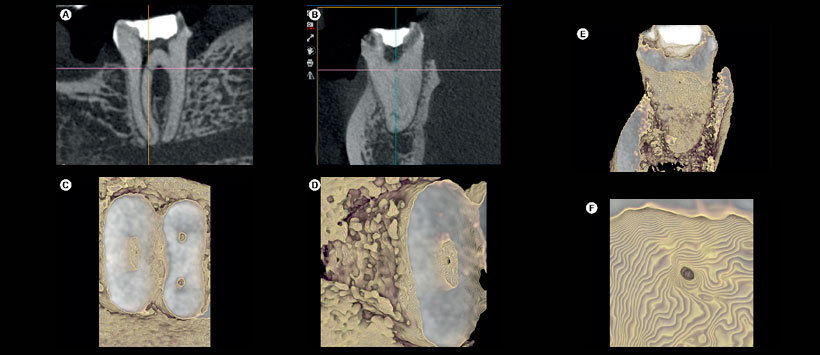

Figura 2: (A-B) las imágenes de e-Vol DX CBCT que muestran el diente n. ° 21 con artefactos de contraste blanco evitan la visualización de una fractura de raíz vertical y ocultan una rarefacción lateral; (C-F) En las imágenes CBCT producidas con un filtro para el contraste normal de la escala de grises, se reducen las áreas claras y la fractura radicular vertical palatina se puede identificar más fácilmente. Figura 3: (A-B) Las imágenes de e-Vol DX CBCT revelan un canal lateral en el diente # 37; (C-F) El filtro favorece la visualización de los detalles anatómicos de este canal lateral interno y su superficie externa (ligamento periodontal) se puede ver claramente a mayores aumentos.

Figura 4: (A) Otro filtro transforma las imágenes CBCT en imágenes en modo transparente, como se muestra en el diente # 26; (B-D) Los detalles específicos de la cámara coronal, así como el volumen y las estructuras adyacentes se visualizan claramente.